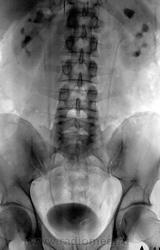

Внутривенная урография.

Уретероцеле слева? Камень слева в нижней группе чашек? Внутривенок давно не видел )

МКБ слева, гидрокаликоз

Добавил бы двусторонний хронический пиелонефрит: форма чашек не нравится.

А. может не уретероцеле, а второй конкремент у устья мочеточника.

Валентин Львович, а на обзорной в устье он на фоне буквы "m" в логотипе сайта? Тогда не увидел... Просто не видно выраженного расширения ЧЛС и мочеточника слева в сравнении с правой стороной

Вы правы уважаемый коллега, именно там.